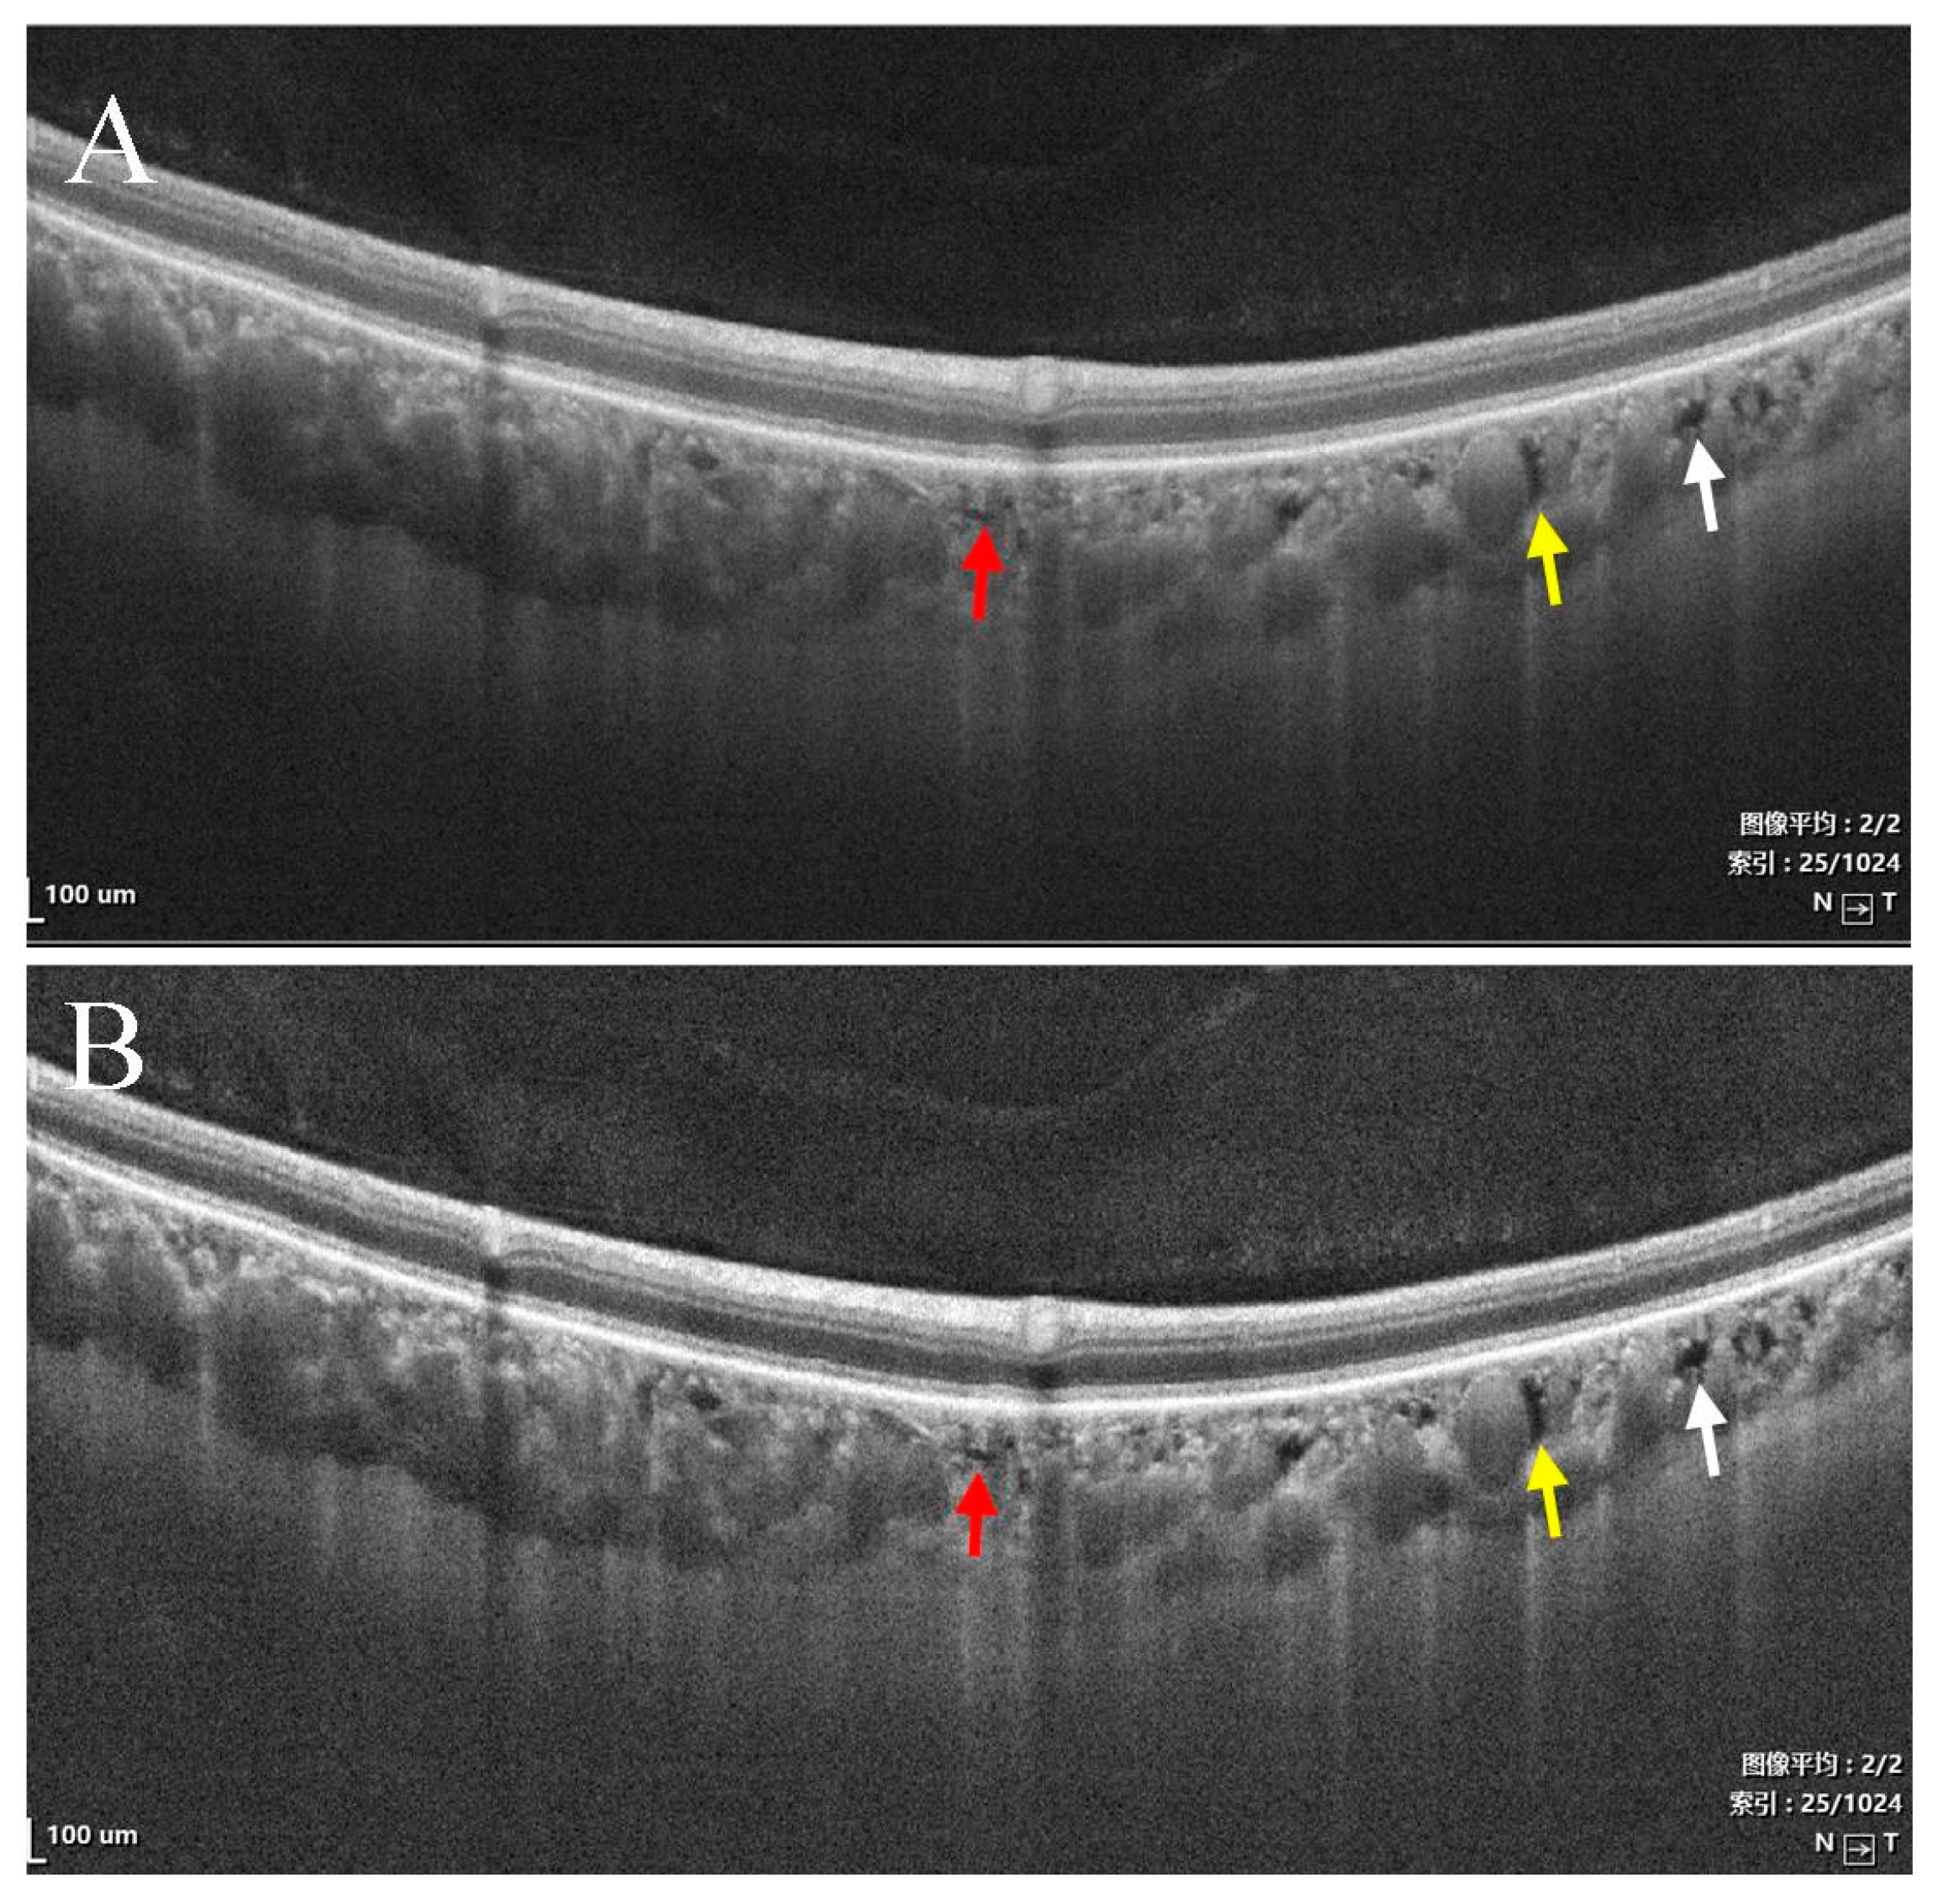

- Type I were small and usually lobulated, occurred in the choroidal capillary and the Sattler’s layers. Depending on the overall choroidal thickness, the upper margin was around 25~50 μm below the Bruch’s membrane (BM) and the lower margin was around 150~200 μm below BM. Furthermore, choroidal caverns outside the macular area were designated subtype Ia (Figure 2) and those within the macular area were designated subtype Ib (Figure 3).